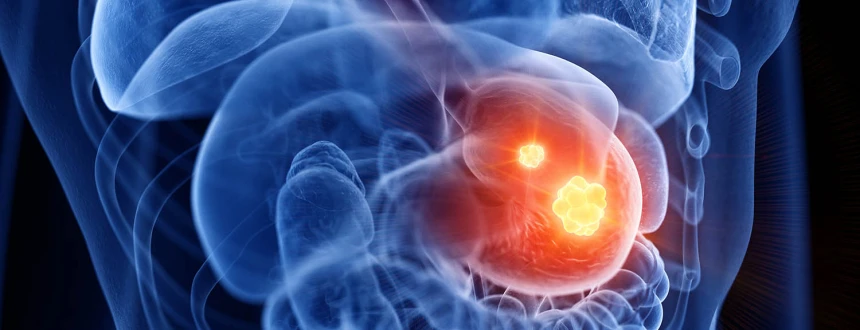

Операция по резекции желудка представляет собой хирургическое вмешательство, в ходе которого удаляется часть органа – от 1/3 до ¾ от его объема. Поводом могут служить как острые патологии, тяжелые заболевания, при которых невозможно нормальное функционирование ЖКТ, так и случаи, когда нужно вылечить ожирение путем снижения количества потребляемой пищи.

- доброкачественная опухоль большого размера;

- рак желудка;

Если необходимо удалить большую опухоль, диагностирован рак, то чаще всего применяется классическая техника. При бариатрии может быть использована щадящая лапароскопическая методика, так как не требуется тотальная резекция.